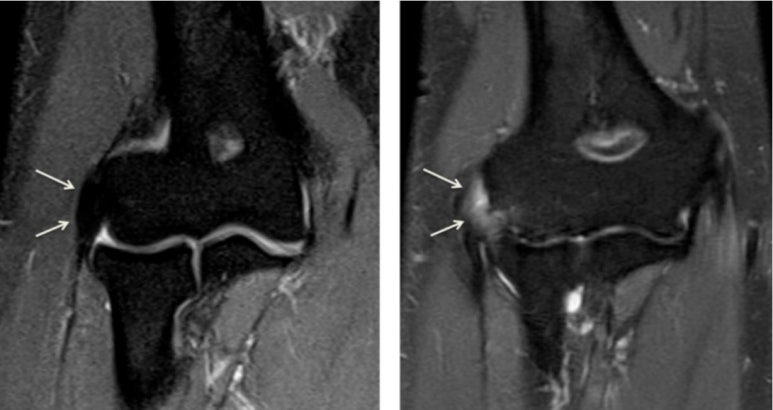

"관절염" 과 "연골 손상"이함께 있습니다.

좌측: 관절낭에 물이 많이 차면서 지방이 위로 떠오릅니다. (Fat pad sign) / 우측: MRI상 관절염으로 물이 많이 보입니다.

출처: https://radiologykey.com/musculoskeletal/